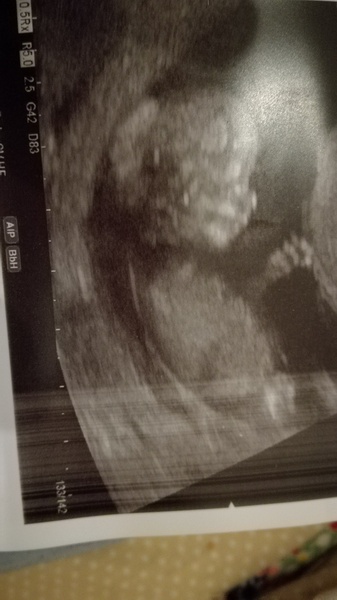

No sure why it's rotated. But here's my baby! A real actual wriggly baby!! In my tummy!! I still can't believe there's a baby inside. My due date has been moved forward a day so the 5th now.

Had a nightmare getting to the scan. Left my bag with my notes in the cafe. So after waiting for dhs delayed train ran to the cage, snow starts coming down again to the point I could barely see. Roads are getting covered in snow. Decide to abandon getting to dads to watch ds and bring him with us. I was not a happy bunny! But all worth it when I saw that wriggle baby.

Lovely scan cuppa! Were they ok with you taking your ds?

Beautiful scan Cuppa!

Ah lovely scan @CuppaSarah!

Congrats on your scan @cuppasarah that's such a cute pic - and we're due date buddies now!